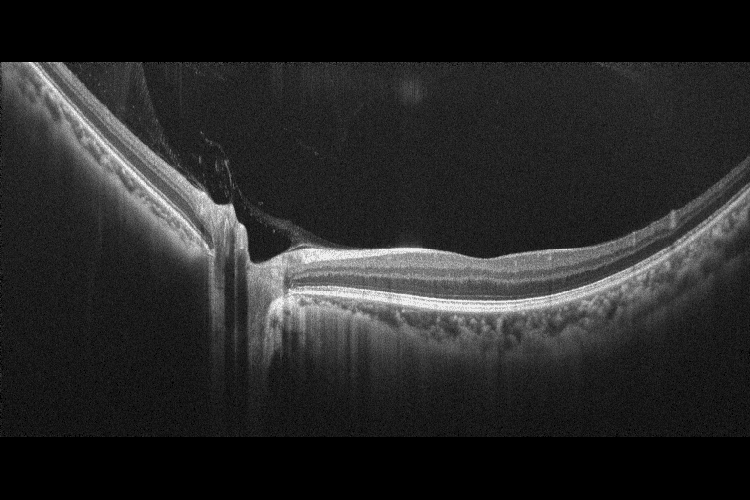

OCT-R1 — це повністю автоматизований пристрій, який поєднує в собі технології спектральної ОКТ та фундус-камери, щоб забезпечити швидке, точне та комплексне обстеження очей.

Оптична когерентна томографія (ОКТ) високої роздільної здатності та фотографія сітківки високої чіткості об’єднані в доступному ОКТ-пристрої початкового рівня з невеликою площею та гнучким розташуванням, що пропонує перевагу легкого розміщення в будь-якій кімнаті та навіть розміщення в кут, що дозволяє оптимально використовувати доступний простір за допомогою сенсорного екрану.

Xephilio OCT-R1 включає функцію усереднення, яка дозволяє комбінувати до 50 множинних сканувань для усунення будь-якого оптичного шуму за допомогою автоматичної сегментації з підтримкою ШІ. Він здатний робити дуже великі ділянки сканування 14,7 мм × 13,4 мм із дуже високою роздільною здатністю 1536 A-сканів у ширину.